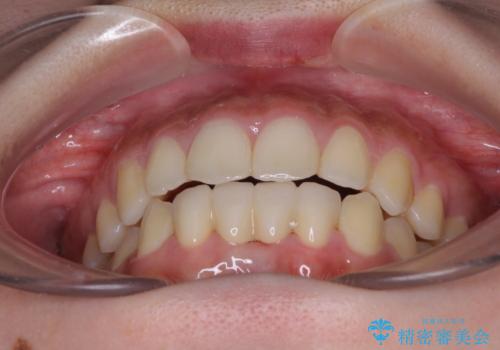

矯正治療終了後に速やかにオールセラミックブリッジを装着していくこととしました。

結婚式の予定があるとのことで、できる限り歯列を整え、挙式直前で残った乳歯を抜歯してブリッジの仮歯を装着するプランを立てたのですが、途中妊娠をされたため、麻酔をするタイミングを検討し、うまく前歯を整えることができました。